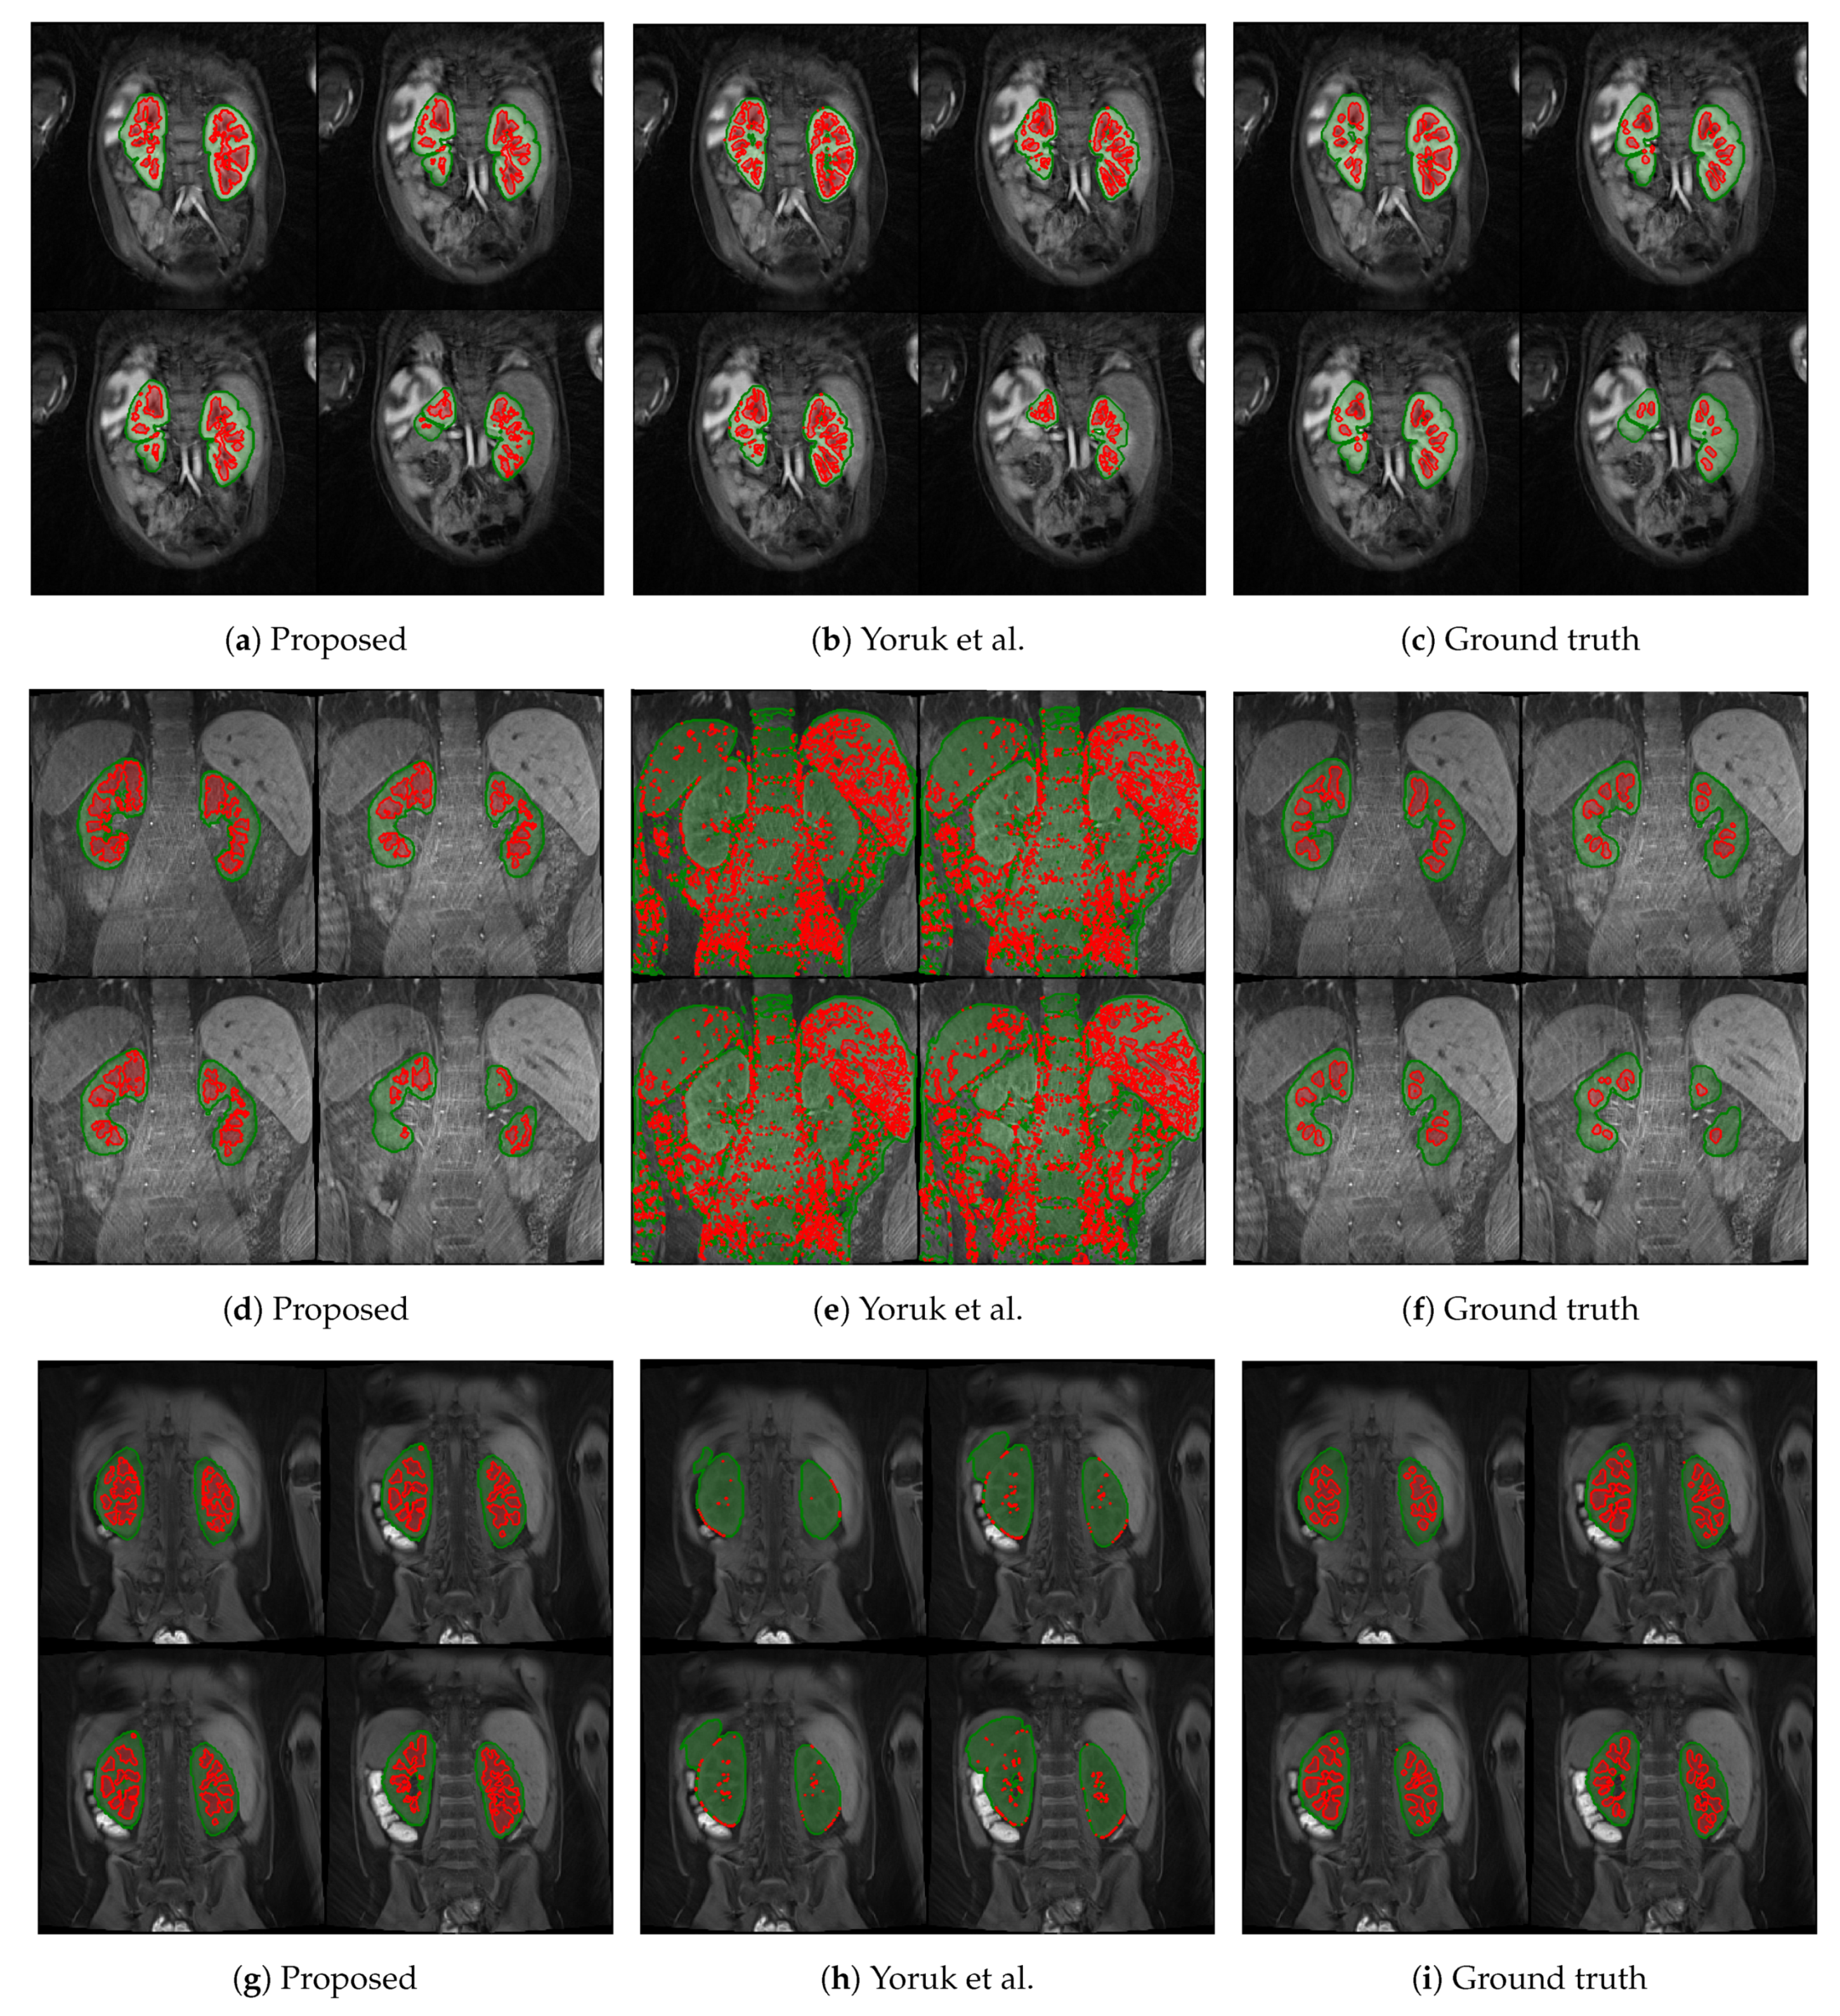

The first columns of Figure 5 and Figure 6 display the medulla (red) and cortex (green) segmentation results in four coronal slices from a single DCE-MRI scan depicting clinically “normal” and “abnormal” kidneys, respectively. Using contrast enhancement via gamma correction and sigmoidal transformation maintained the contextual information while differentiating kidney regions; this occurred mainly in temporal instances where the contrast between DCE-MR imaged renal compartments was low but enough to capture boundary differences where the medulla and cortex edges were in contact.

Figure 5.

Medulla and cortex segmentation results of three different clinically “normal” kidneys. The first column (a,d,g) shows the results from the proposed approach; the second column (b,e,h) shows the respective results using the baseline approach from Yoruk et al. [16]; the third column (c,f,i) shows the respective ground truth.

The proposed renal segmentation approach outperforms a baseline method [16] for extracting the medulla and cortex by approximately 9.3% and 17.1% in mean DSC, respectively, and it boasts higher statistical stability by approximately 15.7% and 12.4%, as shown in Table 3. An available implementation [34] is utilised to reproduce the baseline method. Whereas the baseline method utilises computer vision to extract the whole kidney, the approach proposed in this report employs advancing deep learning to predict highly diverse kidney features, especially of abnormalities. As shown in Figure 6e,h, the algorithm in [16] fails to detect one of the clinically “abnormal” kidneys, whereas the proposed approach has accurately identified the entire organ, as illustrated in Figure 6d and Figure 6g, respectively. Moreover, the baseline approach completely breaks down in a clinically “normal” case, as shown in Figure 5e. In contrast, the robustness of the deep-learning-based model captures both kidneys before renal segmentation is performed, as shown in Figure 5d. A limitation of this particular case (Figure 5d) includes a relatively higher false-negative cortex prediction, resulting in a higher false-positive medulla compared to the ground truth in Figure 5f. Therefore, thresholding parameters would require optimisation to ensure a more robust generalisability. Thus, it would be helpful to expand upon nature-inspired algorithms such as the firefly and swarm intelligence algorithms to determine multilevel thresholds and enhance the compartment segmentation efficiency. In Figure 5h, the binary dilation and erosion strategy in the baseline approach predicts false-positive labels of renal parenchyma, whereas the proposed trained deep learning model accurately localises the kidney. Furthermore, the relatively high concentration of false-negative medulla labels demonstrates the limitations of incorporating the GrabCut and SVM classifier, as in [16]. In comparison, the proposed renal segmentation method exploits intensity enhancement throughout the full temporal dimension of the DCE-MRI to generate the “optimum” medulla labels for the resultant segmentation, as highlighted in Figure 5g.